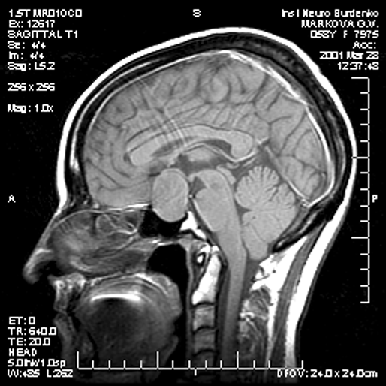

Диагностика опухоли гипофиза включает МРТ, исследование остроты и полей зрения и оценку эндокринологического статуса больного — как клиническую, так и исследование содержания гормонов (передней и задней долей гипофиза, щитовидных, половых, кортизола) в сыворотке крови. Большинство аденом характеризуется низким сигналом на Т1— и высоким — на Т2-взвешенных изображениях (рис. 2–4). Микроаденомы лучше визуализируются после внутривенного введения препарата гадолиния. КТ может иметь значение для уточнения характера костных изменений и размеров турецкого седла.

Рисунок 3. Аденома гипофиза средних размеров (МРТ, Т1-взвешенное изображение, сагиттальная проекция)